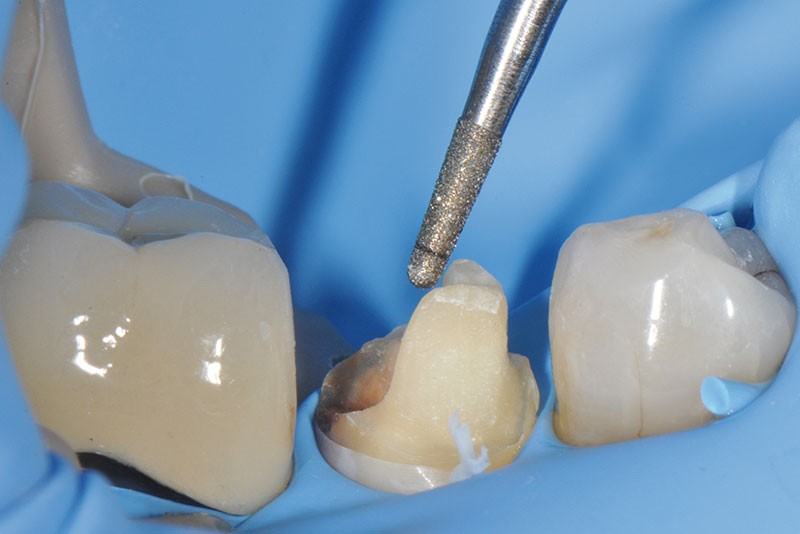

3, 4, 5. La restauration est déposée, les tissus carieux éliminés et la cavité d’accès aménagée avant la réalisation du traitement endodontique. La radiographie postopératoire permet de visualiser l’obturation du canal latéral en regard de la LIPOE.